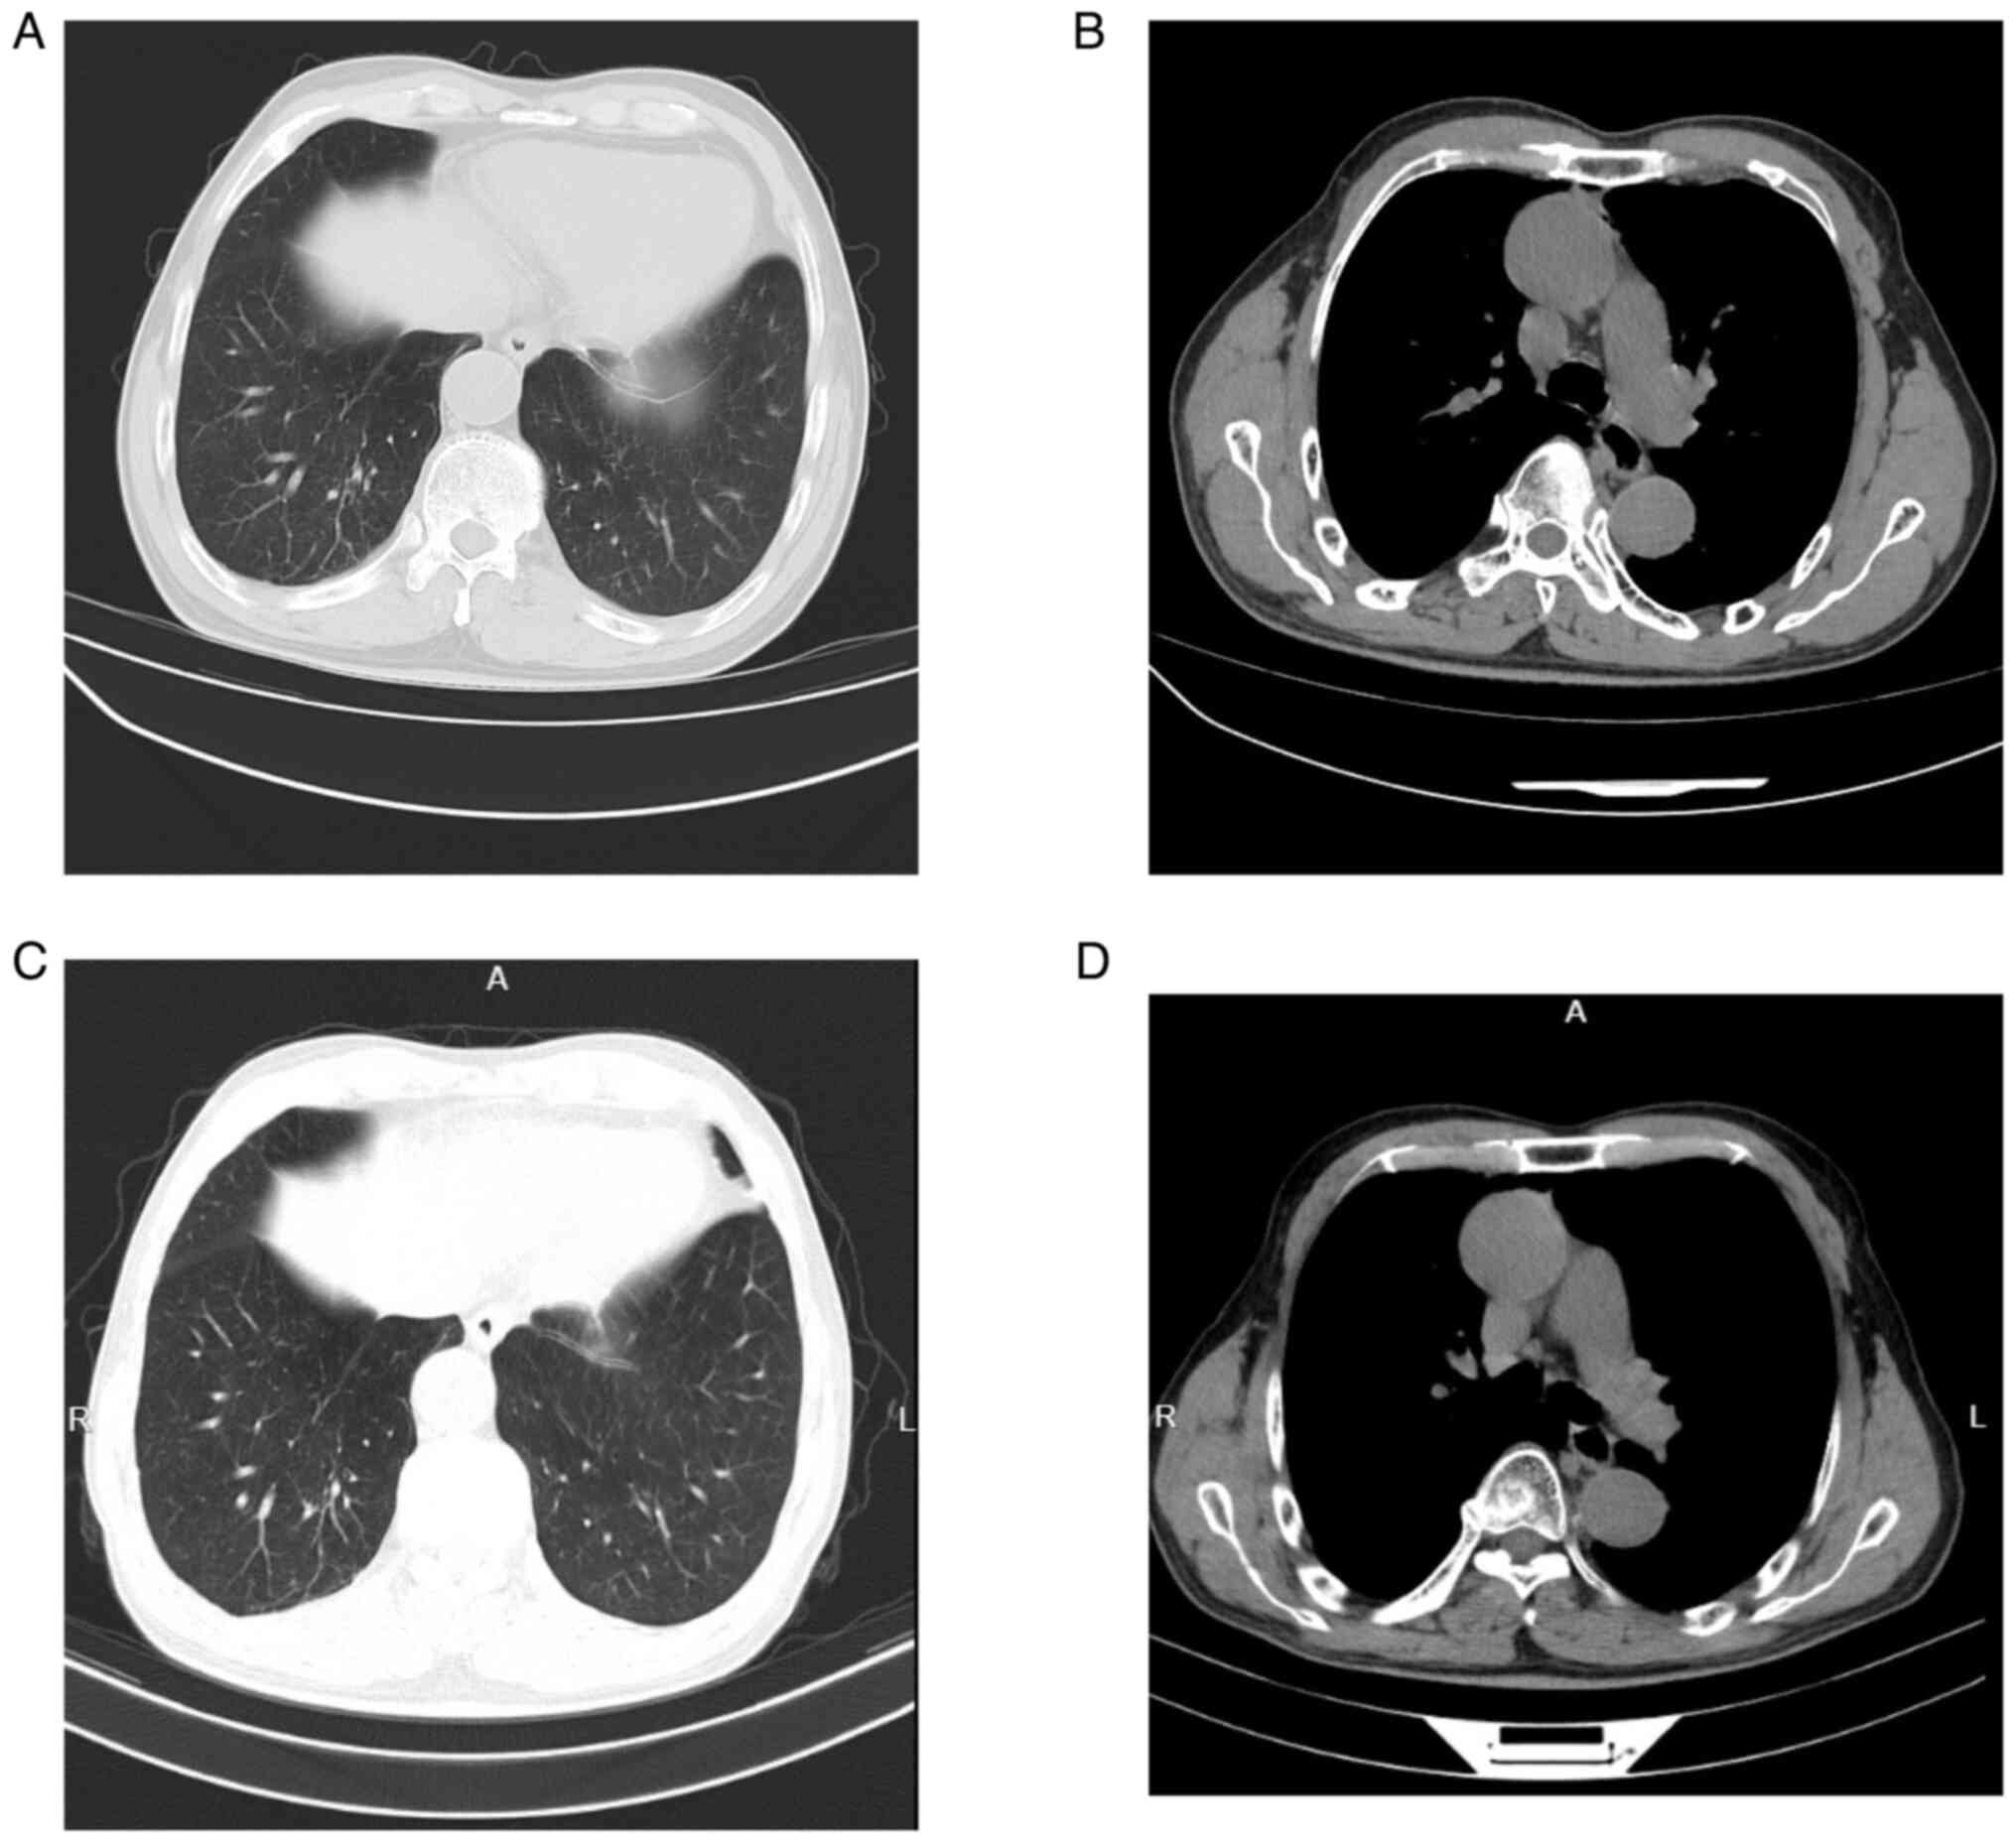

The case of a patient with type B3 thymomacomorbid with Chlamydia psittaci (C. psittaci) pneumonia exhibiting rare features is presented in the current report. The patient was admitted at the Second Affiliated Hospital of Jiaxing University (Jiaxing, China) with a history of direct contact with poultry. Clinical manifestations included fever, shivers, cough, fatigue and poor appetite. Chest computed tomography (CT) indicated right lung pneumonia, while metagenomics next‑generation sequencing using bronchoalveolar lavage fluid confirmed infection with C. psittaci. Additionally, positron emission tomography‑CT suggested the presence of thymoma. After surgery and treatment with doxycycline and imipenem cilastatin, the patient was discharged showing signs of improvement.

Figure 2

Figure 3